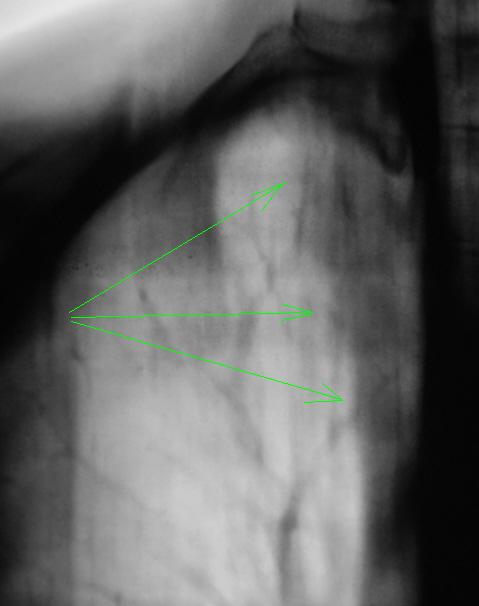

1. Чем объясним снижение прозрачности в медиальных отделах верхушечного сегмента справа?

ИзображениеИзображение